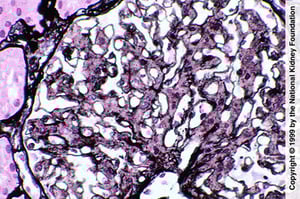

La proliferazione mesangiale è indicativa di glomerulopatia fibrillare; tuttavia, la diagnosi richiede una colorazione rosso Congo negativa, colorazione delle IgG mediante immunofluorescenza e dimostrazione delle fibrille alla microscopia elettronica (colorazione all'argento di Jones, ×400).

La proliferazione mesangiale è indicativa di glomerulopatia fibrillare; tuttavia, la diagnosi richiede una colorazione

Imagine fornita da Agnes Fogo, MD, and the American Journal of Kidney Diseases' Atlas of Renal Pathology (vedi www.ajkd.org).